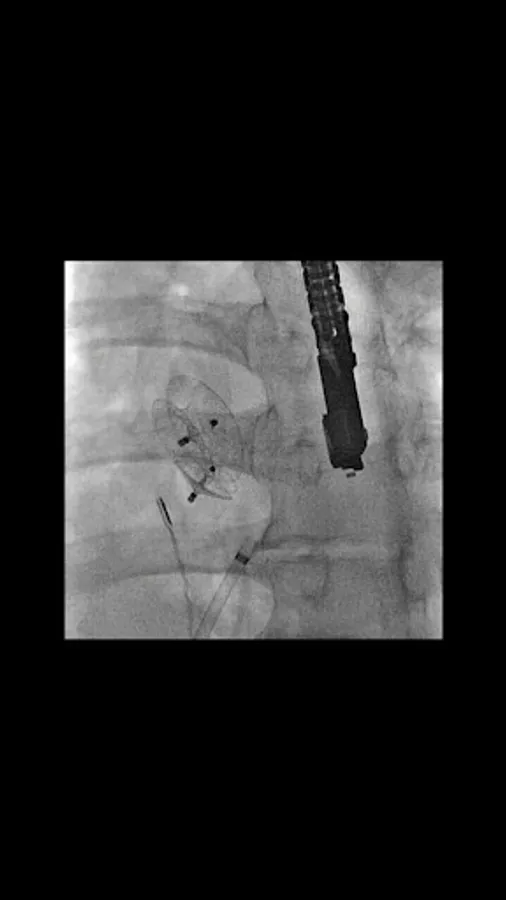

CARDIO3® Atlas of Interventional Cardiology is a CARDIO3®INVASIVE project – reference/learning tool for cardiologists, cardiac surgeons, internists, other physicians evaluating interventional images in cardiology.

- 300 annotated videos (September 2011) and growing